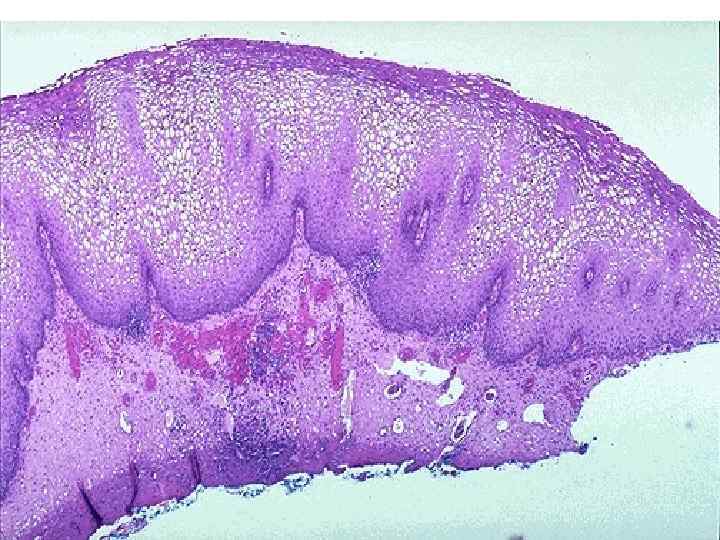

Рак шейки матки n Рост – экзофитный Гистологически – плоскоклеточный рак n